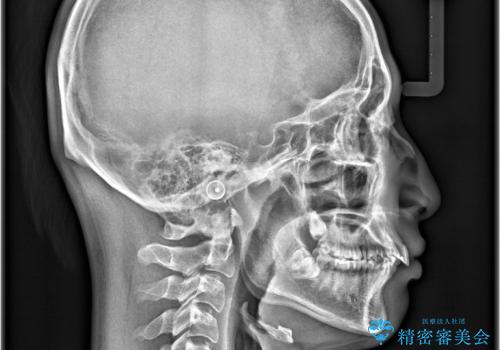

- 咬み合わせの不調和と歯並びのデコボコを主訴にご来院された患者様です。

精密矯正検査の結果、歯を抜かずに非抜歯でワイヤー矯正で治療を行う方針としました。

叢生(歯のデコボコ)の量が多く、加えてディープバイト(過蓋咬合)や重度の捻転も認められたため、リンガルアーチやマイクロインプラントなどの補助装置を併用し、治療を進めました。

治療途中では咬み合わせの改善を目的としてバイトアップを行い、歯の捻転や叢生を改善しつつ、機能的に安定した咬合を獲得しています。

治療期間は3年2ヵ月と比較的長期となりましたが、見た目の歯並びだけでなく、咬み合わせまでしっかり整えた症例です。